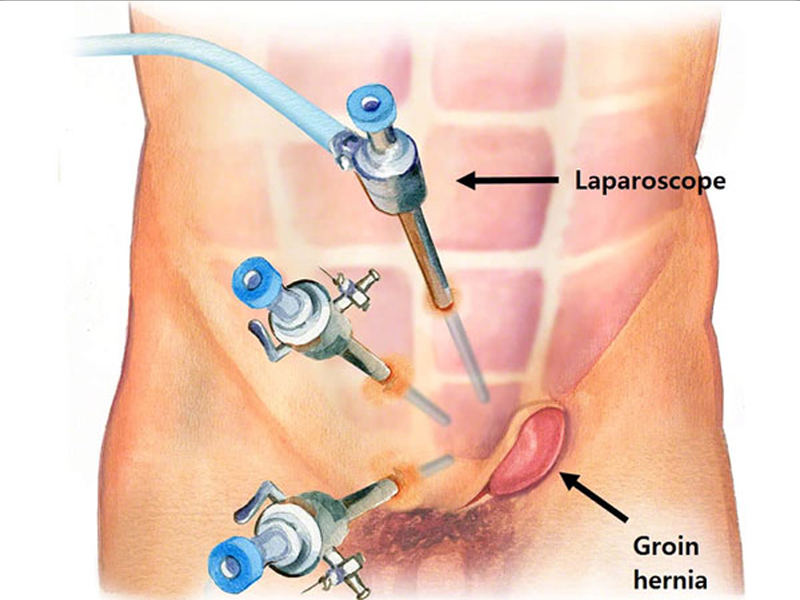

Laparoscopic Hernia Surgery

A hernia occurs when fatty tissue or an organ pushes through a weak place in the surrounding connective tissue...

Laparoscopic Surgery

The process takes its name from the laparoscope, a slender tool that has a tiny video camera and light on the end. When a surgeon inserts it through a...